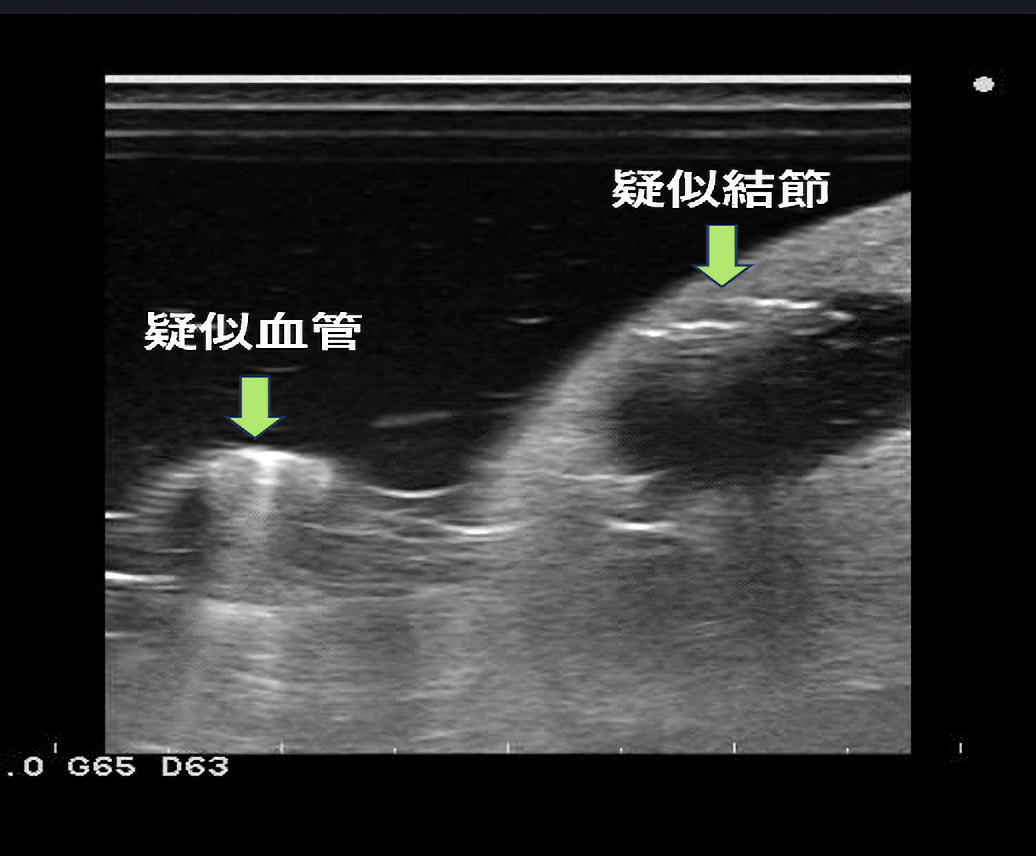

作製したモデルは、超音波下で腎臓の皮質・髄質に該当する部分のコントラストは実際の腎臓のものに類似しており、針穿刺の際にモデル内に針が侵入する様子が超音波下で観察可能です。本モデルの検証のため、岡山大学病院の腎生検経験20例未満の研修生10名に腎生検模擬を実施し、腎生検経験20例以上の腎生検に熟達した腎臓内科医20名がその様子を観察あるいは模擬を実施しました。また、腎生検模擬後に全参加者にアンケート調査を実施しました。その結果、90%の研修生が今回の腎生検模擬によって患者への腎生検に対する不安が軽減されると回答しました。

軟質エラストマー成型品/甲状腺穿刺シミュレーター (製品名:せんしろう)